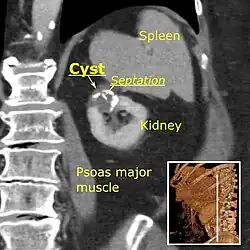

Category IIF

A Bosniak category IIF cyst. This one is 3 cm wide, with calcifications within its wall, seen as very radiodense (white in this presentation) areas in its margins. There is also a septation which is calcified. Yet, the cyst does not show enhancement (uptake of contrast).